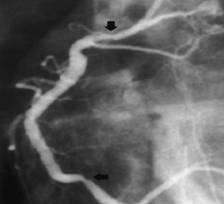

Aspect angiografic de suferintå de CD